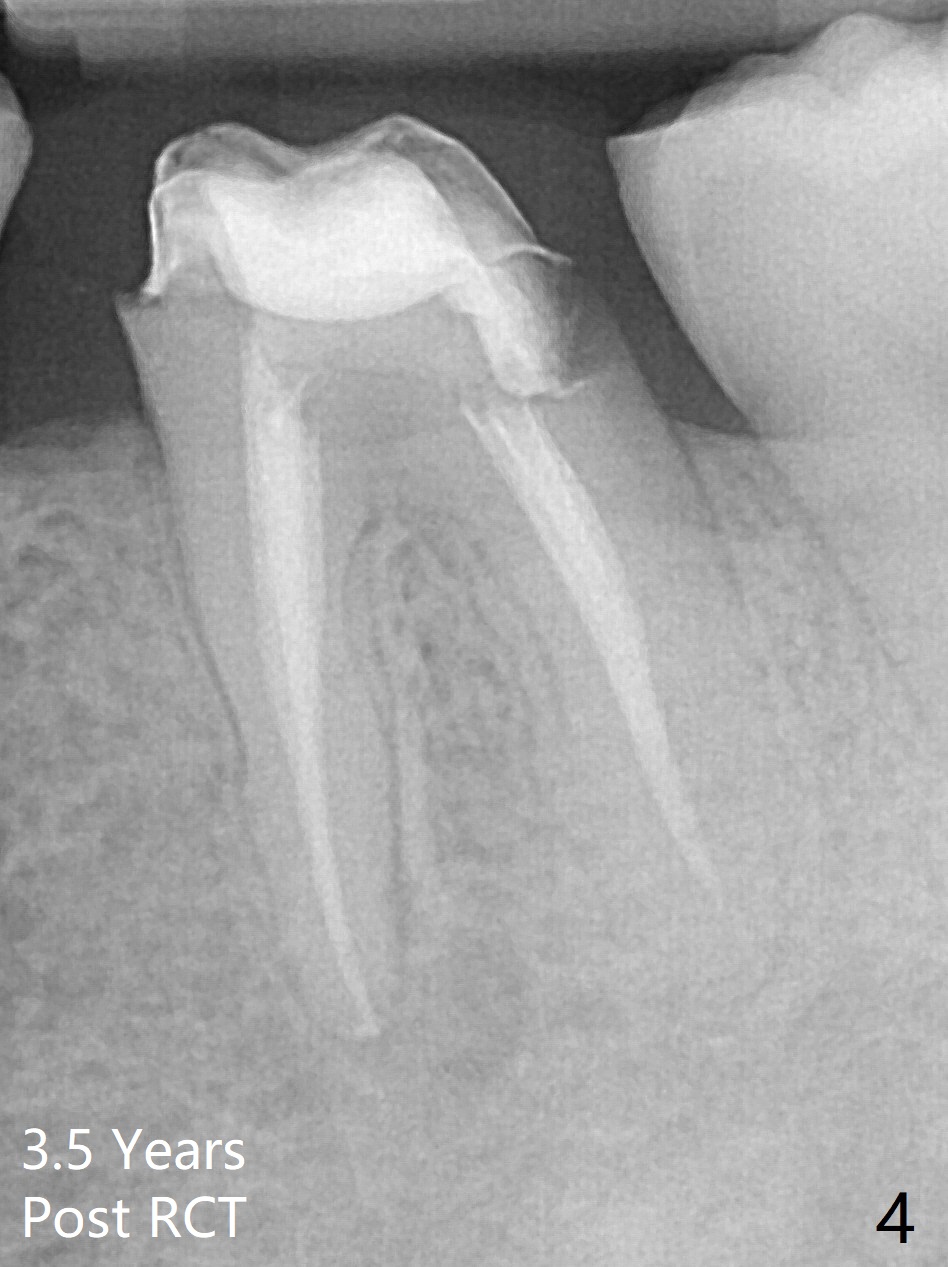

A 29-year-old man has chronic apical perio-dontitis at #19 (Fig.1) for 5 years before RCT with apical buccal swelling (Fig.2). Three days post RCT a fistula develops (Fig.3); curettage is performed. Crown is prepared 3.5 years later (Fig.4). Bitewing is taken immediately before cementation (Fig.5). There is no leakage 2 years 8 months post cementation (Fig.6,7) or periapical radiolucency 6 years 3 months post RCT (Fig.8). Return to Professionals Xin Wei, DDS, PhD, MS 1st edition 11/27/2019, last revision 11/28/2019